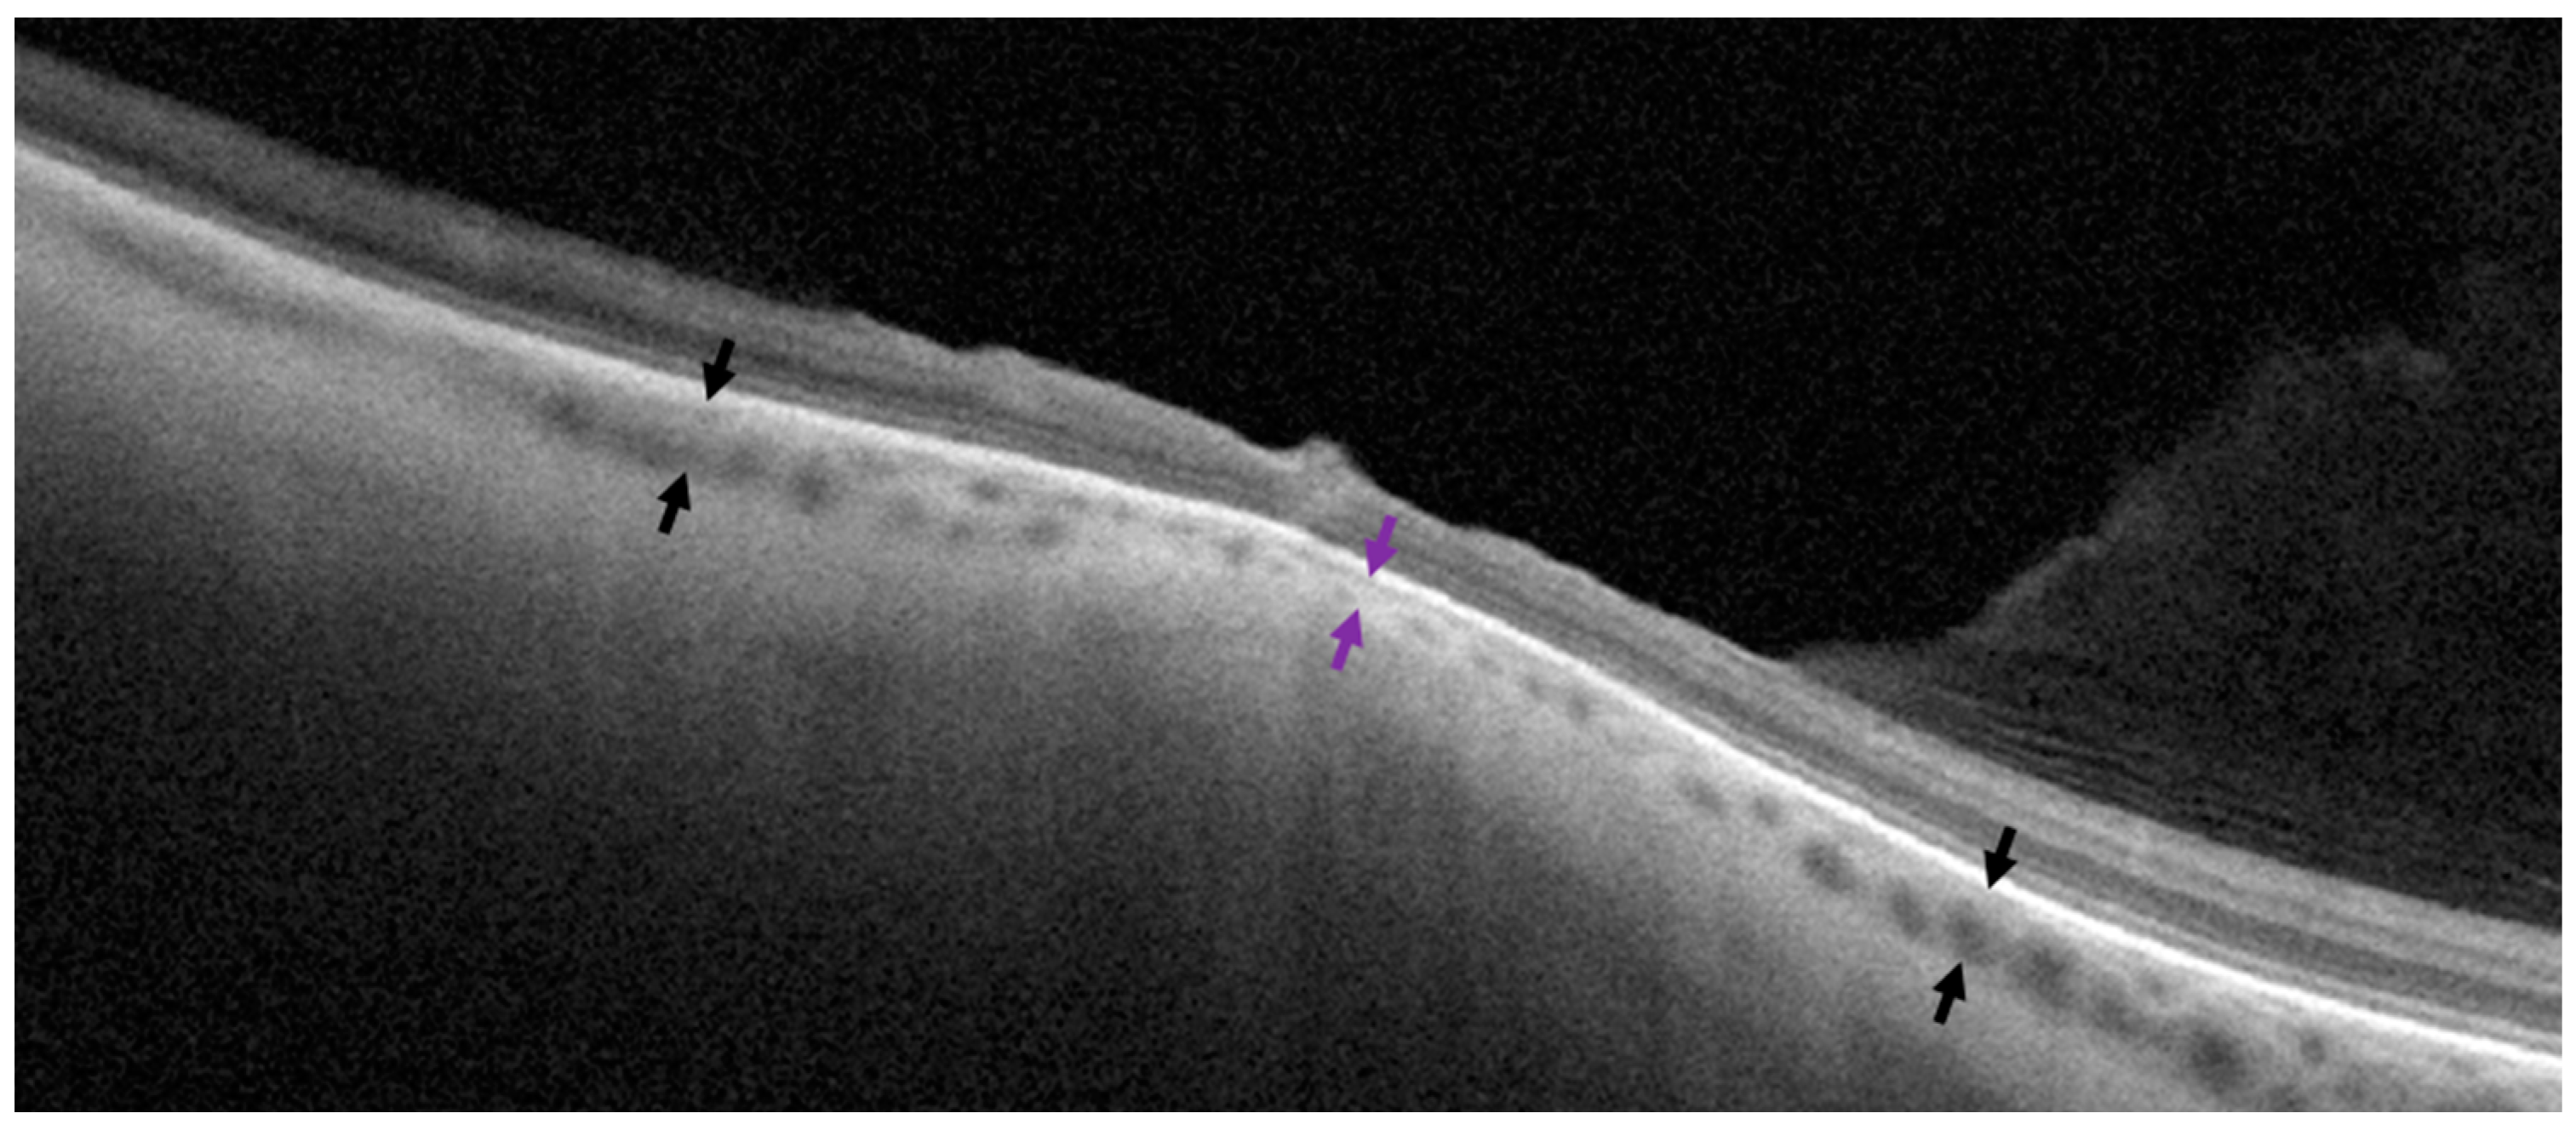

Figure 2. Measurement of choroidal thickness on a cross-sectional optical coherence tomography scan. Purple arrows show choroidal thickness in the middle of the lesion. Black arrows represent choroidal thickness in unaffected neighboring regions on both sides of the lesion.